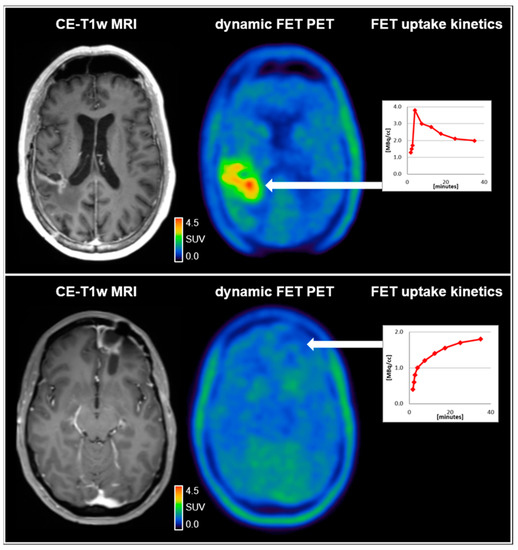

- Ceccon, G.; Lohmann, P.; Stoffels, G.; Judov, N.; Filss, C.P.; Rapp, M.; Bauer, E.; Hamisch, C.; Ruge, M.I.; Kocher, M.; et al. Dynamic O-(2-18F-fluoroethyl)-L-tyrosine positron emission tomography differentiates brain metastasis recurrence from radiation injury after radiotherapy. Neuro-Oncology 2016, 19, 281–288. [Google Scholar] [CrossRef]

- Kunz, M.; Thon, N.; Eigenbrod, S.; Hartmann, C.; Egensperger, R.; Herms, J.; Geisler, J.; La Fougere, C.; Lutz, J.; Linn, J.; et al. Hot spots in dynamic 18FET-PET delineate malignant tumor parts within suspected WHO grade II gliomas. Neuro-Oncology 2011, 13, 307–316. [Google Scholar] [CrossRef]

- Bauer, E.K.; Stoffels, G.; Blau, T.; Reifenberger, G.; Felsberg, J.; Werner, J.M.; Lohmann, P.; Rosen, J.; Ceccon, G.; Tscherpel, C.; et al. Prediction of survival in patients with IDH-wildtype astrocytic gliomas using dynamic O-(2-[18F]-fluoroethyl)-l-tyrosine PET. Eur. J. Nucl. Med. Mol. Imaging 2020, 47, 1486–1495. [Google Scholar] [CrossRef]

- Thon, N.; Kunz, M.; Lemke, L.; Jansen, N.L.; Eigenbrod, S.; Kreth, S.; Lutz, J.; Egensperger, R.; Giese, A.; Herms, J.; et al. Dynamic18F-FET PET in suspected WHO grade II gliomas defines distinct biological subgroups with different clinical courses. Int. J. Cancer 2014, 136, 2132–2145. [Google Scholar] [CrossRef]

- Vettermann, F.; Suchorska, B.; Unterrainer, M.; Nelwan, D.; Forbrig, R.; Ruf, V.; Wenter, V.; Kreth, F.-W.; Herms, J.; Bartenstein, P.; et al. Non-invasive prediction of IDH-wildtype genotype in gliomas using dynamic 18F-FET PET. Eur. J. Nucl. Med. Mol. Imaging 2019, 46, 2581–2589. [Google Scholar] [CrossRef] [PubMed]

- Suchorska, B.; Giese, A.; Biczok, A.; Unterrainer, M.; Weller, M.; Drexler, M.; Bartenstein, P.; Schüller, U.; Tonn, J.-C.; Albert, N.L. Identification of time-to-peak on dynamic 18F-FET-PET as a prognostic marker specifically in IDH1/2 mutant diffuse astrocytoma. Neuro-Oncology 2018, 20, 279–288. [Google Scholar] [CrossRef]

- Kebir, S.; Rauschenbach, L.; Galldiks, N.; Schlaak, M.; Hattingen, E.; Landsberg, J.; Bundschuh, R.A.; Langen, K.-J.; Scheffler, B.; Herrlinger, U.; et al. Dynamic O-(2-[18F]fluoroethyl)-L-tyrosine PET imaging for the detection of checkpoint inhibitor-related pseudoprogression in melanoma brain metastases. Neuro-Oncology 2016, 18, 1462–1464. [Google Scholar] [CrossRef] [PubMed]